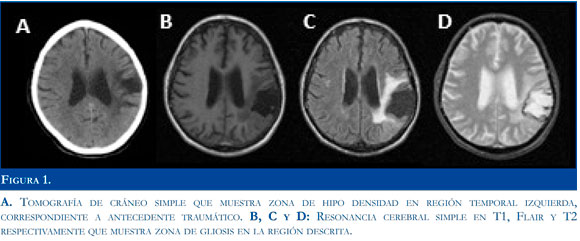

Se solicitaron los paraclínicos necesarios para descartar patología orgánica relacionada con estecuadro, se halló leve hiponatremia y leve hiperglucemia, las cuales fueron corregidas; pero el paciente persistió con los síntomas. Psiquiatría sospechó demencia vascular, con delirium asociado y se inició haloperidol gotas dosis total de 2,5mg/ día, el paciente continuó con síntomas, en especial risas inmotivadas hasta 4 veces en una hora, y luego recuperaba su estado basal. Al examen mental era un paciente orientado en persona, desorientado en tiempo y lugar, con memoria episódica alterada, pensamiento lógico y concreto, sin actitud alucina-toria, no se hallaron otras anormalidades al examen neurológico, la tomografía computarizada de cráneo y la resonancia magnética cerebral mostraron zona de encefalomalasia temporal izquierda y dilatación ventricular ipsilateral compensatoria, y por sospecha de evento ictal se realizó electroencefalograma en el cual se encontró descarga epileptiforme ictal de 2 minutos de duración en el hemisferio cerebral izquierdo de predominio parasagital, lo que se consideró como crisis focales simples de tipo automatismos atribuidos a lesión estructural traumática, se inició ácido valpróico 1,5 gr/día, y se controlaron los episodios (Figuras 1 y 2).